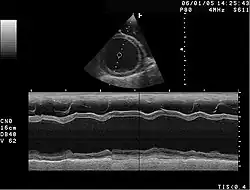

Die hypertrophische Kardiomyopathie (HCM) ist durch eine meist asymmetrische Verdickung der Muskulatur der linken Herzkammer charakterisiert.

Die dilatative Kardiomyopathie (DCM), bei der zunächst der linke Ventrikel (Herzkammer) (im Endstadium auch alle Herzhöhlen) erheblich erweitert ist (das Herz kann mit einem großen schlaffen Sack verglichen werden). Die Wandstärken sind meist nicht oder nur geringfügig verdickt (hypertrophiert). Das Herz zieht sich nur eingeschränkt zusammen (= systolische Funktionseinschränkung), oft kombiniert mit asynchronem Kontraktionsablauf der Kammern, bedingt durch eine Störung der Erregungsleitung infolge Linksschenkelblocks. Zahlenmäßig sind abgelaufene Herzmuskelentzündungen und chronischer Alkoholmissbrauch die häufigsten Ursachen. Es gibt auch angeborene Formen. Sekundäre Formen sind die „ischämische DCM“ infolge einer koronaren Herzerkrankung und der Endzustand eines Hochdruckherzens. Die DCM ist ein häufiger Grund für eine Herztransplantation, wenn der Zustand des Patienten mit Medikamenten, Koronarintervention oder kardialer Resynchronisationstherapie (CRT) nicht ausreichend gebessert werden kann. Die Diagnose wird nach klinischem Verdacht mit den typischen Symptomen durch bildgebende Verfahren (Echokardiografie, MRT, MSCT) und feingeweblich (Myokardbiopsie) gesichert. Eine koronare Herzkrankheit muss durch eine Herzkatheteruntersuchung ausgeschlossen werden, da sich hieraus eine kurative Behandlungsmöglichkeit der Ursache ergeben könnte.

Bei Katzen ist die hypertrophe Kardiomyopathie die am häufigsten beobachtete Form der Erkrankung. Sie wird auch als Folgeerscheinung einer Schilddrüsenüberfunktion beobachtet (thyreotoxische Kardiomyopathie). Eine Sonderform gleicht der hypertroph-obstruktiven Kardiomyopathie des Menschen. Daneben sind auch die restriktive und die dilatative Kardiomyopathie bei Katzen beschrieben. Letztere wird aber als sekundäre Kardiomyopathie eingestuft, da sie die Folgeerscheinung eines Mangels an dem für Katzen sehr wichtigen Taurin ist. Da industrielle Fertigfuttermittel mit diesem Inhaltsstoff angereichert sind, wird diese Form der Erkrankung bei Katzen zunehmend seltener beobachtet. Weiterhin existieren Übergangsformen, die sowohl Zeichen einer Erweiterung als auch Zeichen einer Hypertrophie zeigen. Sie werden als intermediäre Kardiomyopathie bezeichnet. Katzen mit einer Herzerkrankung haben ein hohes Risiko für eine arterielle Thromboembolie.[13]